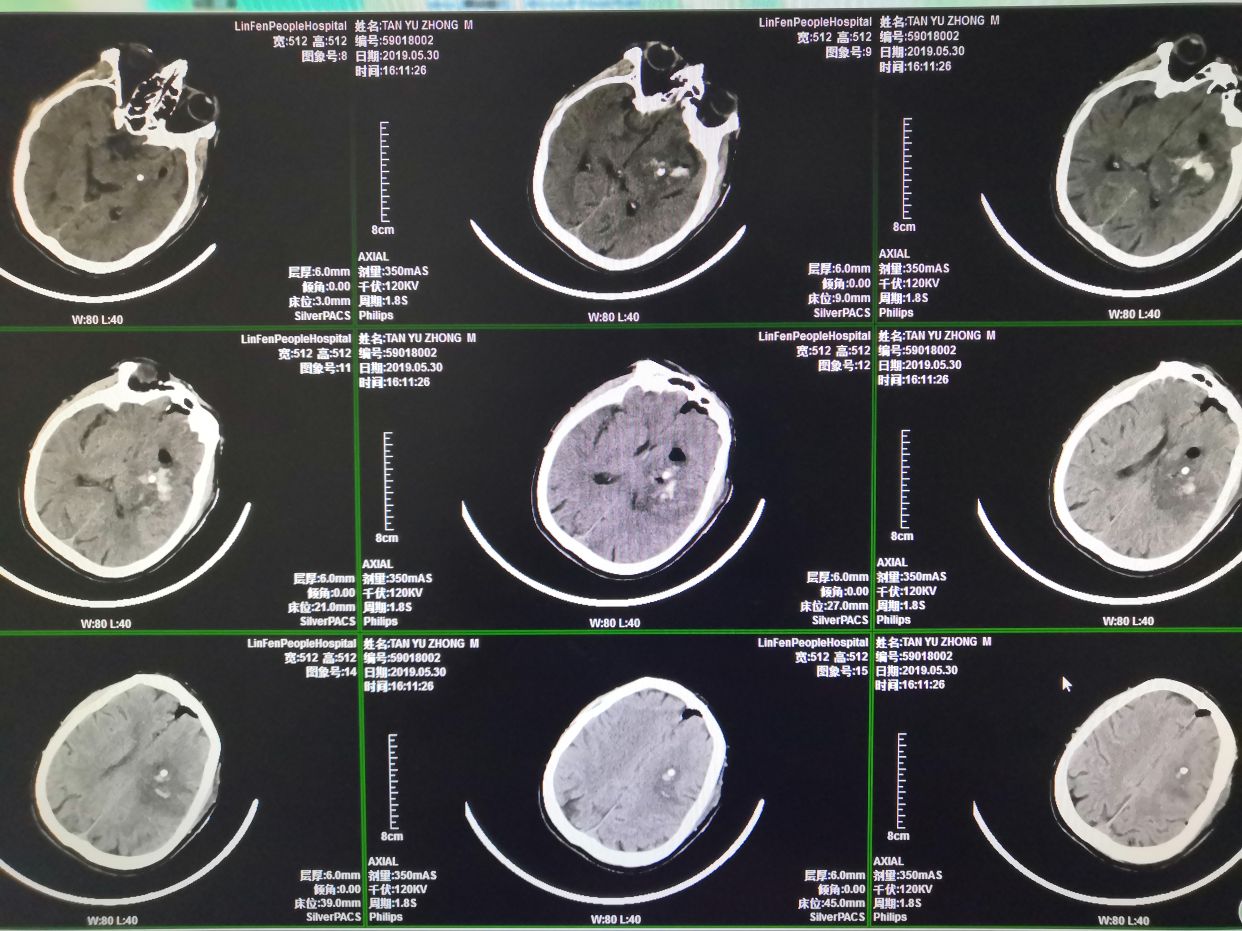

患者男性,主因:“发现意识不清伴右侧肢体无力3小时”急诊入院。患者于入院前3小时被家人发现瘫倒在发上,当时患者意识欠清,言语不能,右侧肢体无力,伴小便失禁,后被120急救后送至当地医院行颅脑CT检查,结果提示:左侧底节区脑出血,转诊至我院,复查颅脑CT后,我科急诊以:“左侧底节区脑出血高血压病3级极高危组”收治入院。查体:血压166/105mmHg,神志嗜睡,呼叫睁眼,失语,可简单遵嘱配合,双侧瞳孔等大圆,约2.5m,对光反射迟钝,口角向左侧轻度歪斜,左侧肢体肌力4级,右侧肢体肌力0级,肌张力下降,右侧肢体腱反射减弱,右侧巴氏征(+)。颅脑CT左侧底节区脑出血。诊断左侧底节区脑出血,高血压病三级极高危。

术前多田公式测量出血量约为63ml